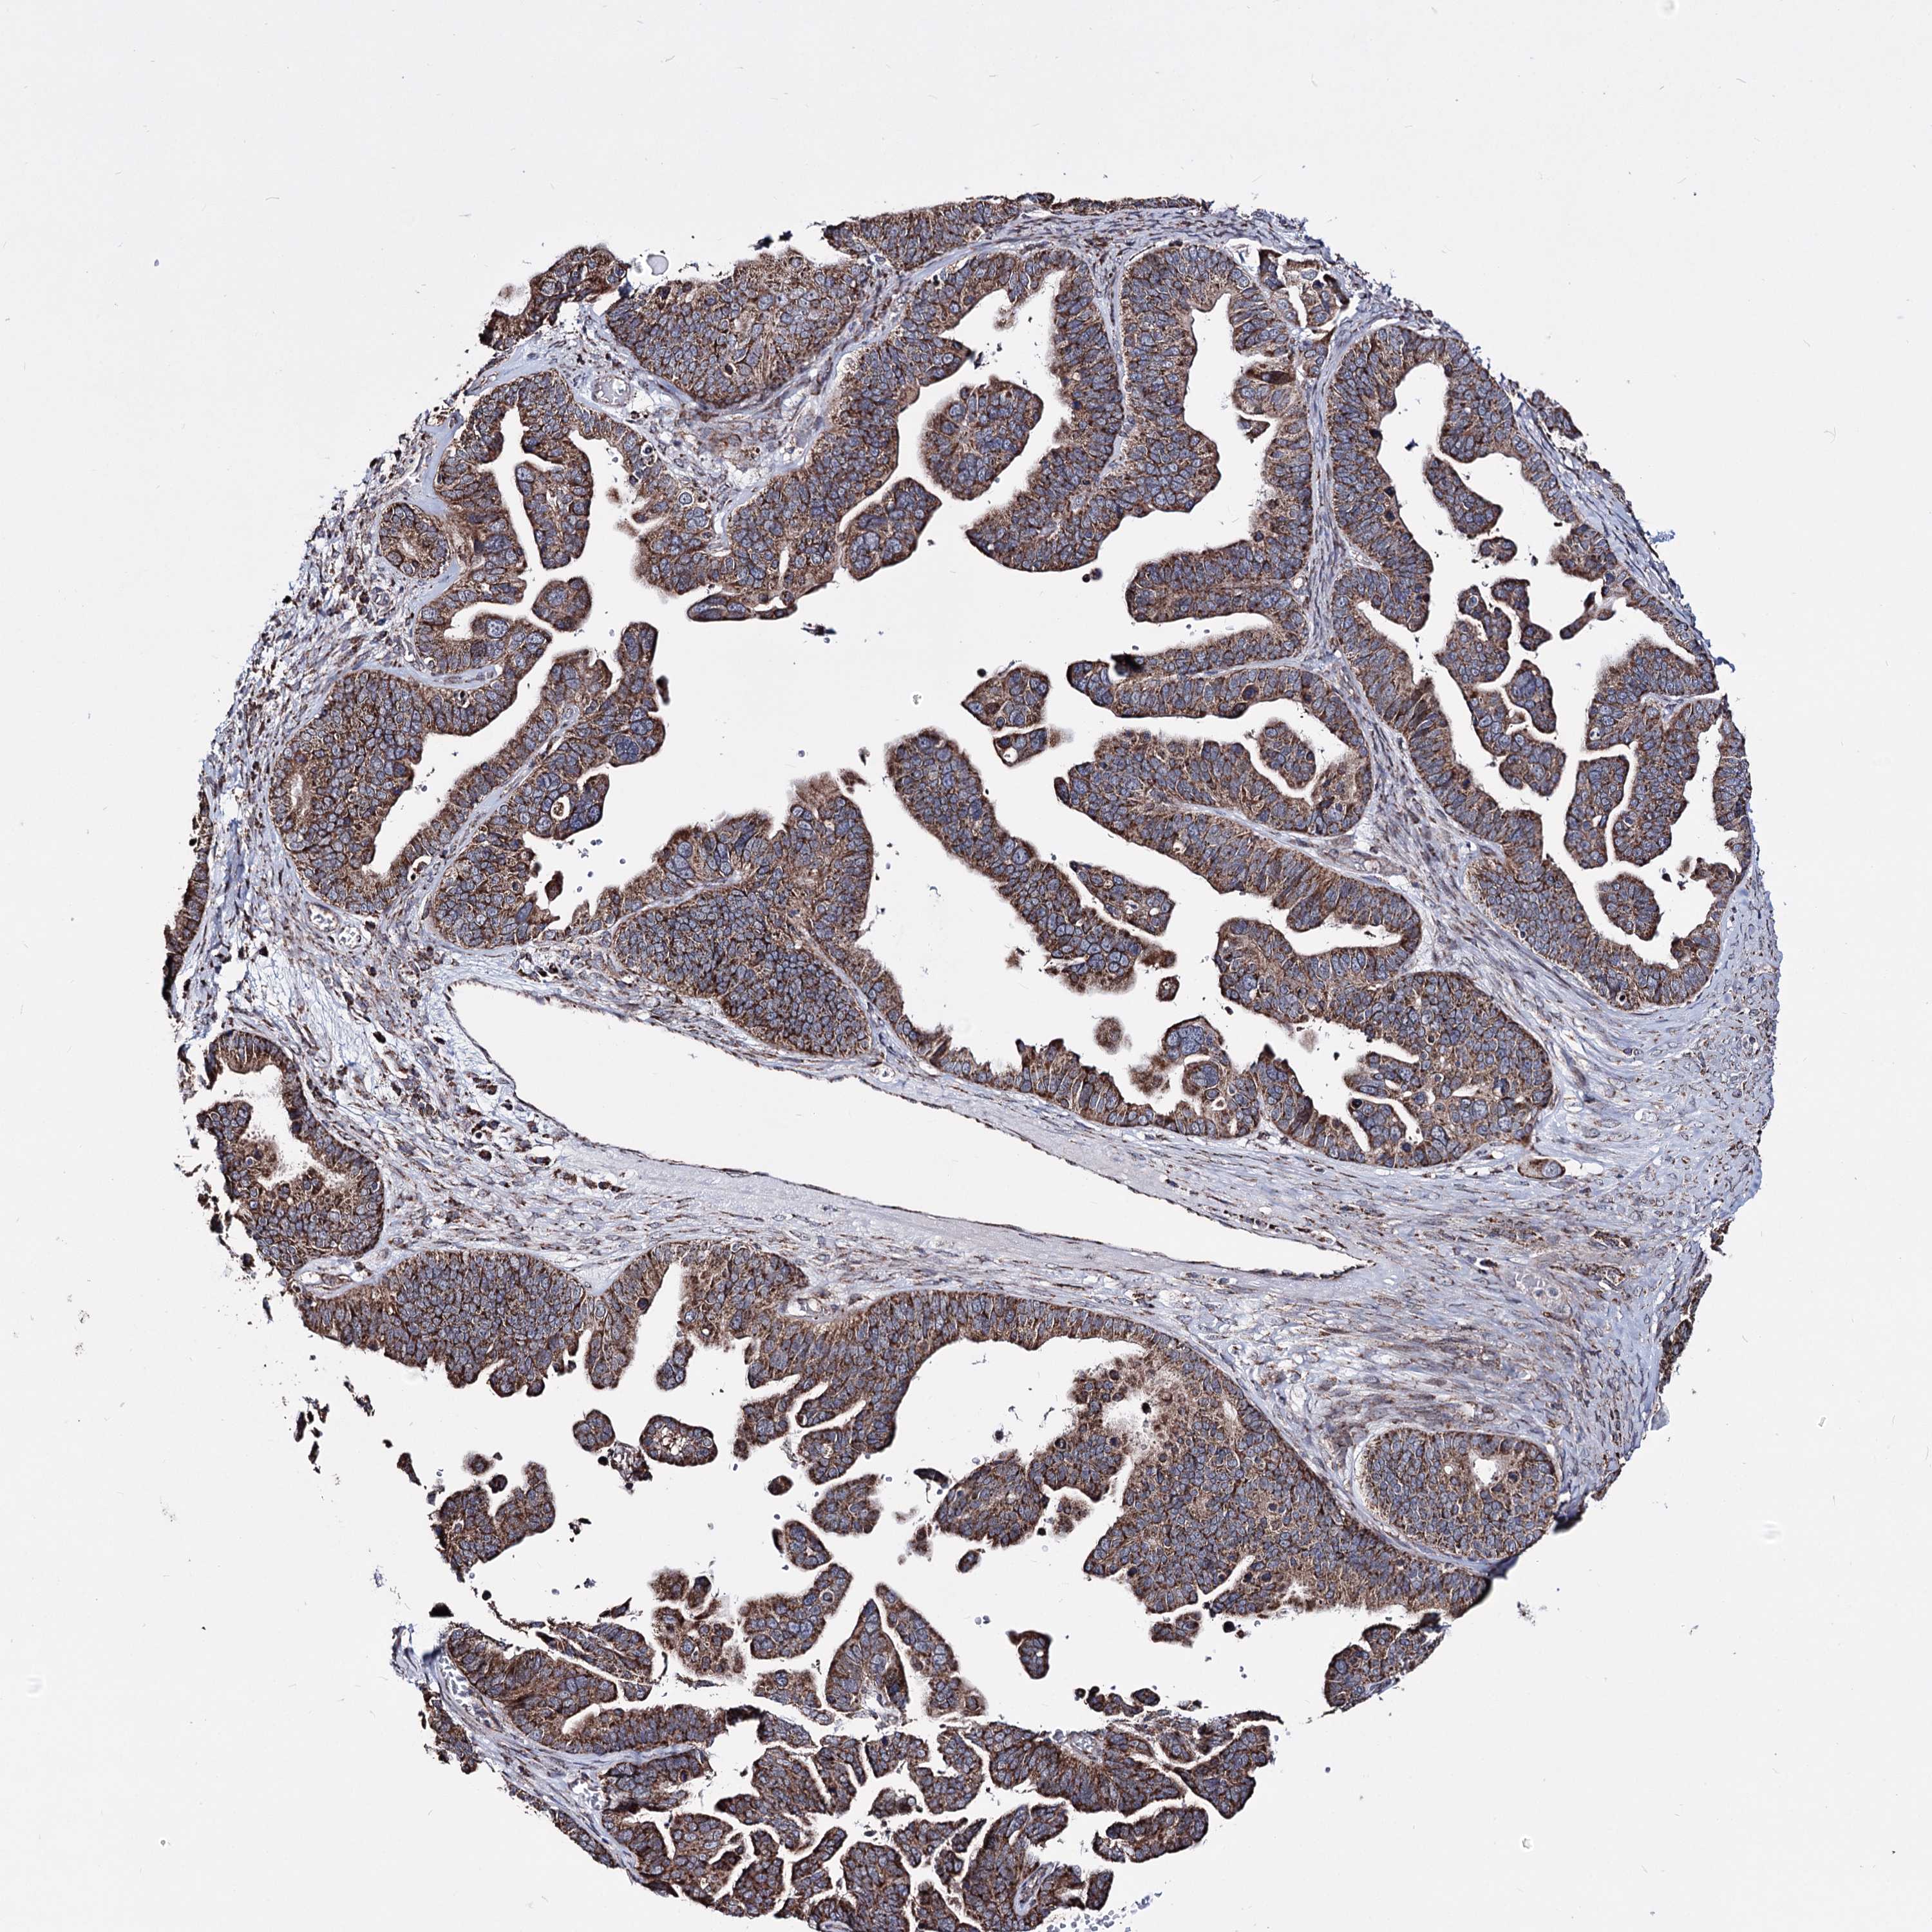

OVARIAN CANCER - Protein expressioni

A mouse-over function shows sample information and annotation data. Click on an image to view it in a full screen mode. Samples can be filtered based on level of antibody staining by selecting one or several of the following categories: high, medium, low and not detected. The assay and annotation is described here.

Note that samples used for immunohistochemistry by the Human Protein Atlas do not correspond to samples in the TCGA dataset.

Antibody stainingi

Antibody staining in the annotated cell types in the current human tissue is reported as not detected, low, medium, or high, based on conventional immunohistochemistry profiling in selected tissues. This score is based on the combination of the staining intensity and fraction of stained cells.

Each image is clickable and will lead to virtual microscopy that enables deeper exploration of all samples and also displays staining intensity scores, fraction scores and subcellular localization as well as patient and tissue information for each sample.

Antibody HPA038122

Staining

High

Medium

Low

Not detected

Intensity

Strong

Moderate

Weak

Negative

Quantity

>75%

75%-25%

<25%

None

Location

Nuclear

Cytoplasmic/membranous

Cytoplasmic/membranous,nuclear

Cystadenocarcinoma, serous, NOS

Carcinoma, endometroid

Cystadenocarcinoma, mucinous, NOS

Carcinoma, NOS